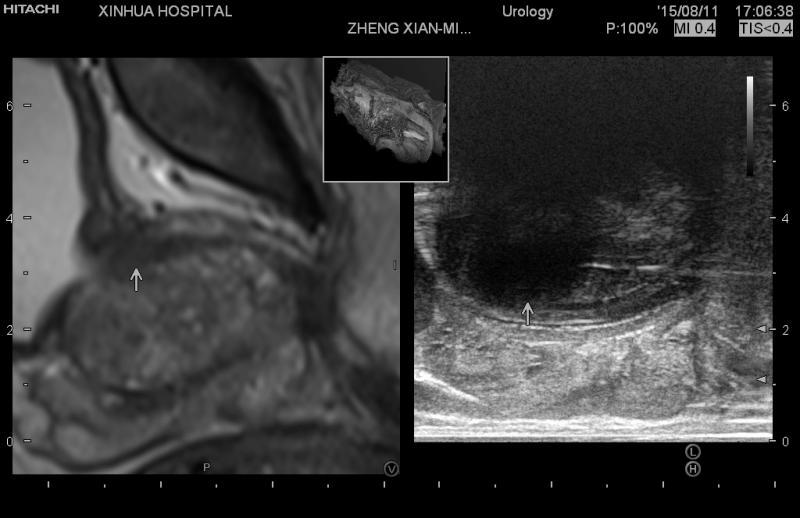

新华医院泌尿外科治疗团队给出了另一个治疗建议——冷冻消融术。这种手术是在经直肠超声的引导下,从会阴部将多根冷冻针置入到前列腺腺体中,利用高压氩气通过冷冻消融针在组织内快速释放,局部温度可迅速下降达到零下150-170摄氏度,细胞内液体和周围的小血管内血液结冰;然后利用高压氦气的快速释放,使组织间的温度迅速回升到零上25摄氏度。温度快速的变化会导致细胞膜破裂,细胞发生死亡。冷冻消融治疗原则上可适用于各个年龄段的人群,由于其微创性,特别适合一些不能耐受手术的高龄高危患者。同时,这种手术对麻醉要求也比较低,相比以往的射频消融术而言,冷冻消融术中患者因不用耐受高温而减少疼痛,因此可在腰麻甚至局麻下条件下进行,不需要全身麻醉不需要上呼吸机。

手术由康健和沈海波医生施行,在超声指引下,手术精准,并在30分钟内顺利完成。应老先生术后只在医院里观察了一天,第二天早上就回家了。两周后他回医院拔掉导尿管,再次检查发现,应老先生的前列腺无论是癌组织还是增生组织都一并消融液化,老先生再也不用坐在马桶上憋尿,体验了一把久违的酣畅淋漓。